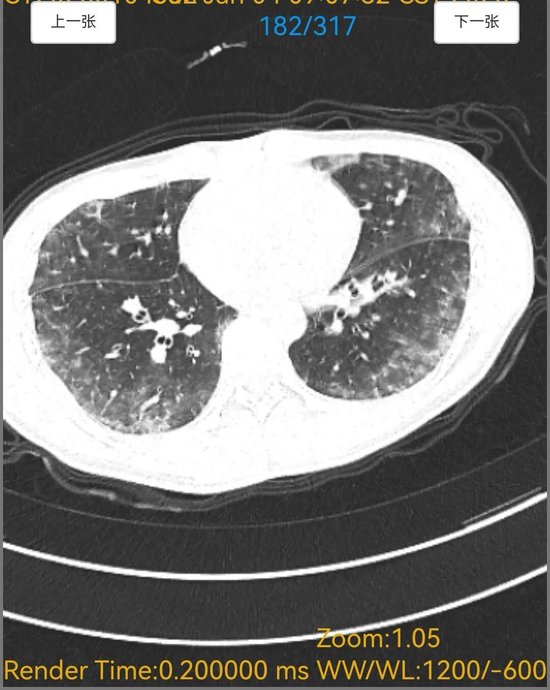

6天胸闷气短、5天持续高热,18岁的小宋被紧急送入平原县人民医院呼吸内科,胸部CT检查结果让接诊医生忧心不已,双肺布满大片“毛玻璃”阴影,呈现弥漫性病变,提示肺部正遭受严重侵袭。更棘手的是,常规感染筛查中,细菌、病毒等常见病原体检测均为阴性,病因成谜,治疗陷入困境。

诊断明确后,呼吸内科医师团队制定了针对性极强的精准治疗方案。令人惊叹的疗效随之出现,在针对性药物治疗仅5天后,患者复查胸部CT。影像对比显示,原本遍布双肺的弥漫性“毛玻璃”阴影已基本完全吸收